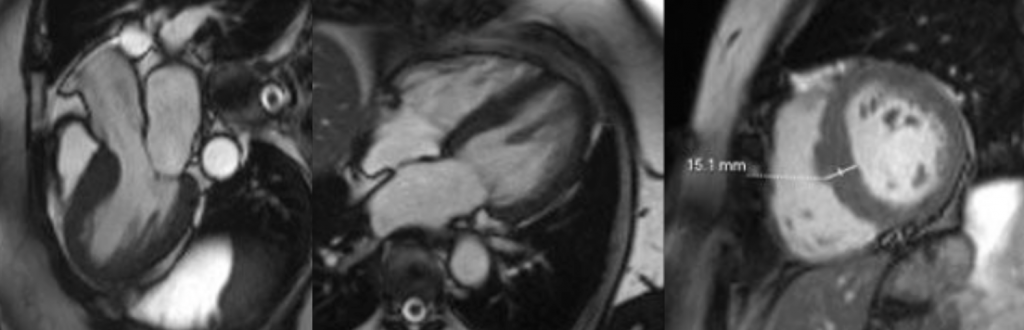

Cine cardiac MRI images

Short-axis and long-axis cine images demonstrating global concentric left ventricular hypertrophy with basal septal thickness measuring approximately 1.5 cm at end diastole, without evidence of left ventricular outflow tract obstruction or systolic anterior motion of the mitral valve.